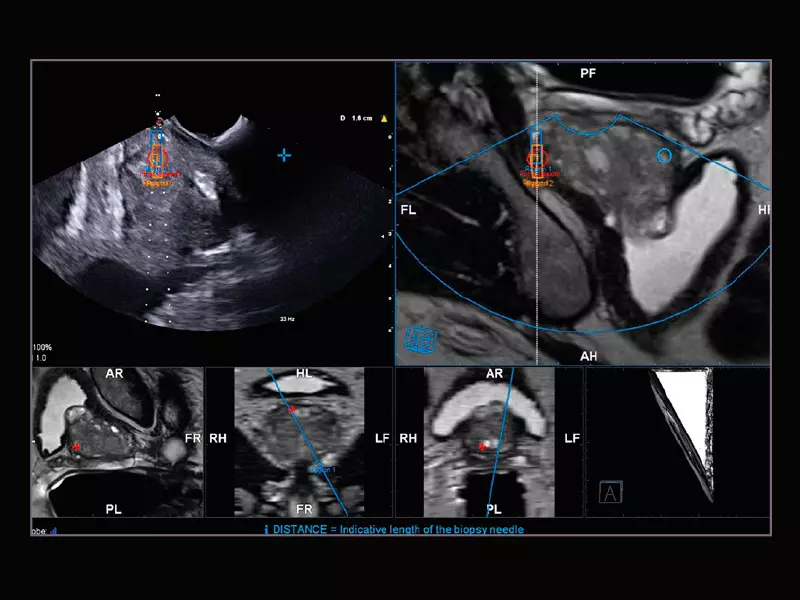

MyLab™E80 - Urofusion - TP Biopsy

MyLab™E80 - Urofusion - TP Biopsy

MyLab™X90 - UroFusion Automatic segmentation of the prostate MRI/US, followed by autoregistration of both modalities for targeted biopsies

MyLab™X90 - UroFusion Automatic segmentation of the prostate MRI/US, followed by autoregistration of both modalities for targeted biopsies